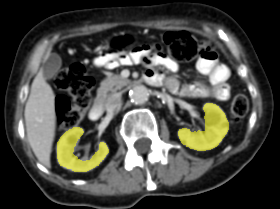

Refer to caption

(a) Input CT scan

(b) Annotations format 1

(c) Annotations format 2

Figure 2: Example illustrating the different annotation formats. Each subfigure shows the same axial section, with overlays depicting the annotations: (a) shows the axial CT section. (b) shows the annotations in format 1: parenchyma and kidney abnormalities as a single structure (yellow overlay). (c) shows the annotations in format 2: parenchyma (yellow overlay) and kidney abnormalities (red overlay) as different structures. All images have a window center of 60 HU and a window width of 360 HU.

This study utilized two annotation formats, format 1 and format 2, to store the annotations. Format 1 considers the kidney parenchyma and kidney abnormalities as a single class (see Figure 2(b)) while format 2 separates them into two classes (see Figure 2(c)).